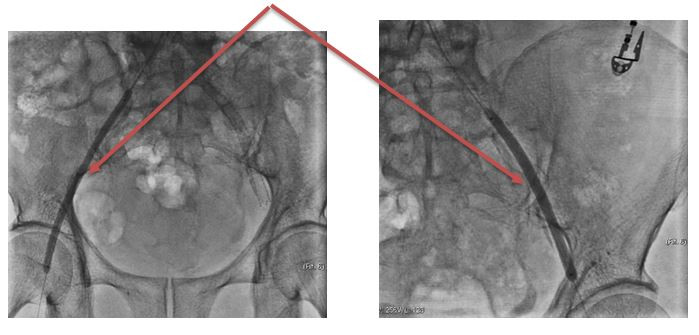

Người bệnh Đ.T.H (sinh năm 1962, Việt Trì) thường xuyên bị đau 2 chân, mỗi lần chỉ đi được tầm 50m, gây khó khăn, bất tiện trong sinh hoạt. Đến khám tại Khoa Can thiệp tim mạch – Trung tâm Tim mạch, người bệnh được chẩn đoán: tắc động mạch chậu 2 bên, đã được chỉ định can thiệp nong bóng, đặt stent động mạch chậu 2 bên. Sau can thiệp 4 ngày, người bệnh đã có thể đi lại bình thường và được ra viện.

Hình ảnh động mạch chậu bị tắc |

| Can thiệp nong bóng động mạch chậu 2 bên |

Động mạch chậu 2 bên thông tốt sau can thiệp |